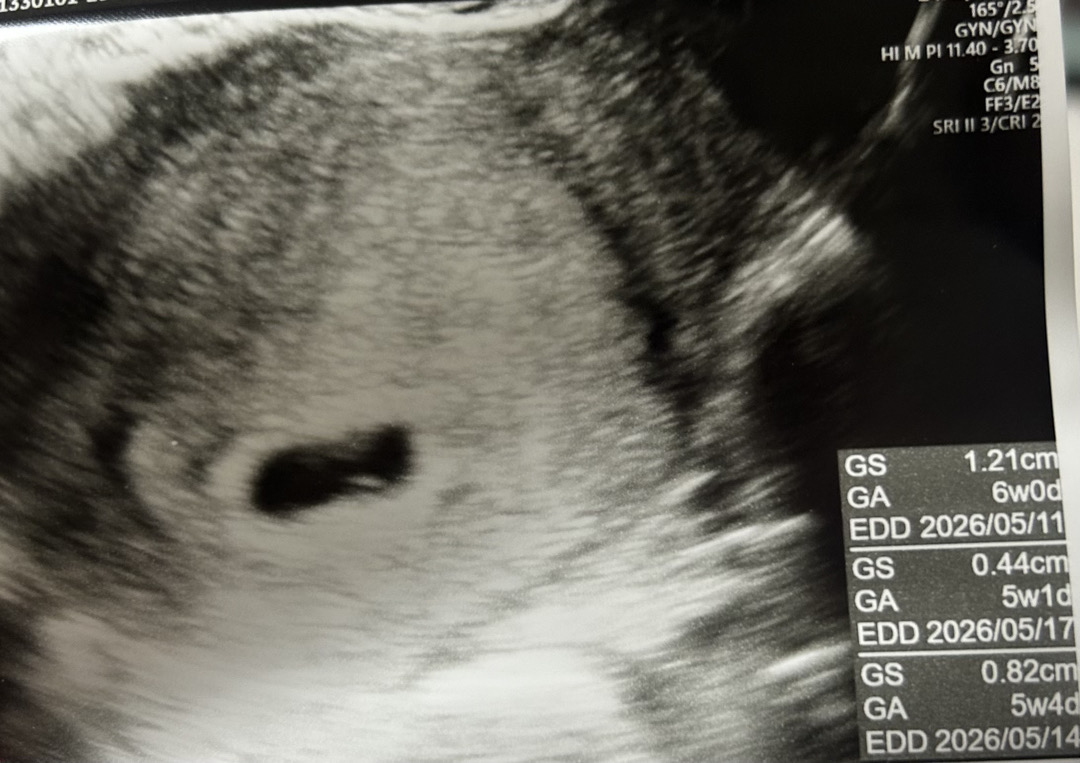

5주 5주일차인데

5주 4일차때 직장에서 조금 무리해서 애기 잘못됐나싶어서 보건소 초음파로 찍었는데 난황이 만들어지고 있는거 같다고 하셨거든요ㅠㅜ (올린사진이 5주4일차입니다! 5주2일차는 산부인과에서 아기집만 보였어요ㅠ) 다음주 금요일 7주0일때 가서 난황이랑 심장소리 들을수있을까요??지금 걱정이 많네요ㅠㅠ 이번주 금요일(6주0일)에 한번 더 가볼까요? 제가 생리가 불규칙이라 주수에 비해 좀 늦는거 같기도 하고 그러네요ㅠㅠ 아직 직장에는 알리지않아서 단축근무도 못하고 평소대로 움직이는건 다 움직이는데 몸이 무리가 가는지 배가 살짝 콕콕거리기도 하지만 다행히 출혈은 없네요.. 첫 임신이라 이것저것 매일 걱정입니다ㅠㅠ